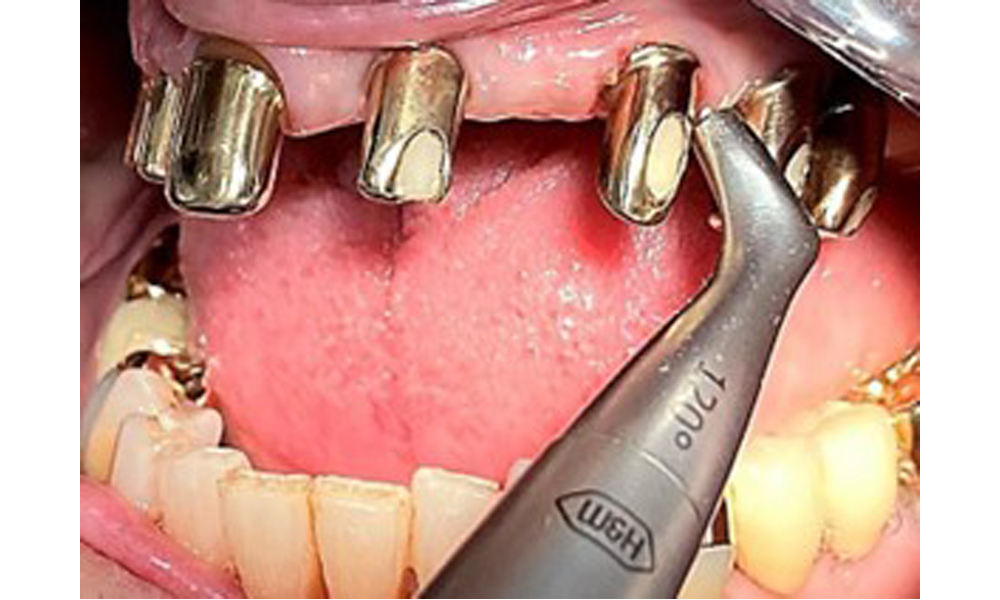

Frontal view with the maxillary denture in situ.

Fig. 1: Frontal view with the maxillary denture in situ.

The patient was fitted with a combined removable maxillary telescopic prosthesis more than 25 years ago (Fig. 1, Fig. 2, Fig. 3) and is very happy with her dentures. The patient has an adequate fixed denture for the mandible (Fig. 4).

The dental findings are as follows: Combined removable implant and tooth-supported telescopic prostheses on implants 15, 13, 21, 23, 24, 25 and tooth 11 (Fig. 1, Fig. 2, Fig. 3). The patient was fitted with a fixed mandibular denture. Adequate bridges were present over 37 to 34 and 45 to 47 (Fig. 4), the crown margins were intact and there were no active caries. A composite filling with a marginal gap was present on tooth 43. There was mandibular gingival recession, exposing 1 to 3 mm of root surface. This also applies to 11.